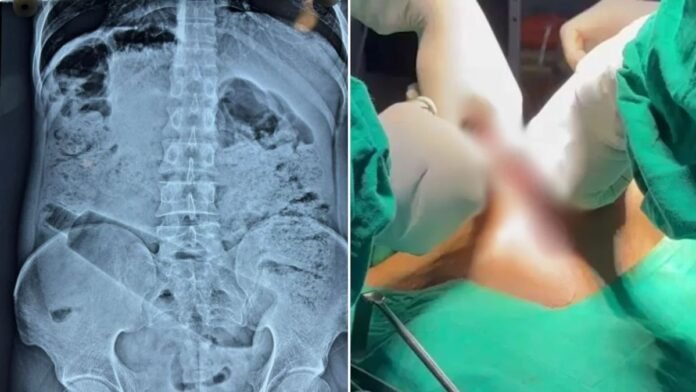

एक्स-रे में दिखी बोतल, सर्जरी कर बचाई गई जान

गांव लौटने के बाद युवक ने डॉक्टर से इलाज कराया, जहां Dr. Vipin Verma ने उसका अल्ट्रासाउंड और एक्स-रे कराया। जांच रिपोर्ट में पेट के अंदर बोतल साफ दिखाई दी, जिसके बाद तुरंत सर्जरी का फैसला लिया गया। डॉक्टरों की टीम ने सफल ऑपरेशन कर करीब 15×4 सेंटीमीटर की प्लास्टिक बोतल बाहर निकाल दी। डॉक्टर के मुताबिक, मरीज की हालत गंभीर थी, लेकिन समय रहते ऑपरेशन होने से उसकी जान बचा ली गई। फिलहाल युवक की स्थिति स्थिर बताई जा रही है और वह खतरे से बाहर है।